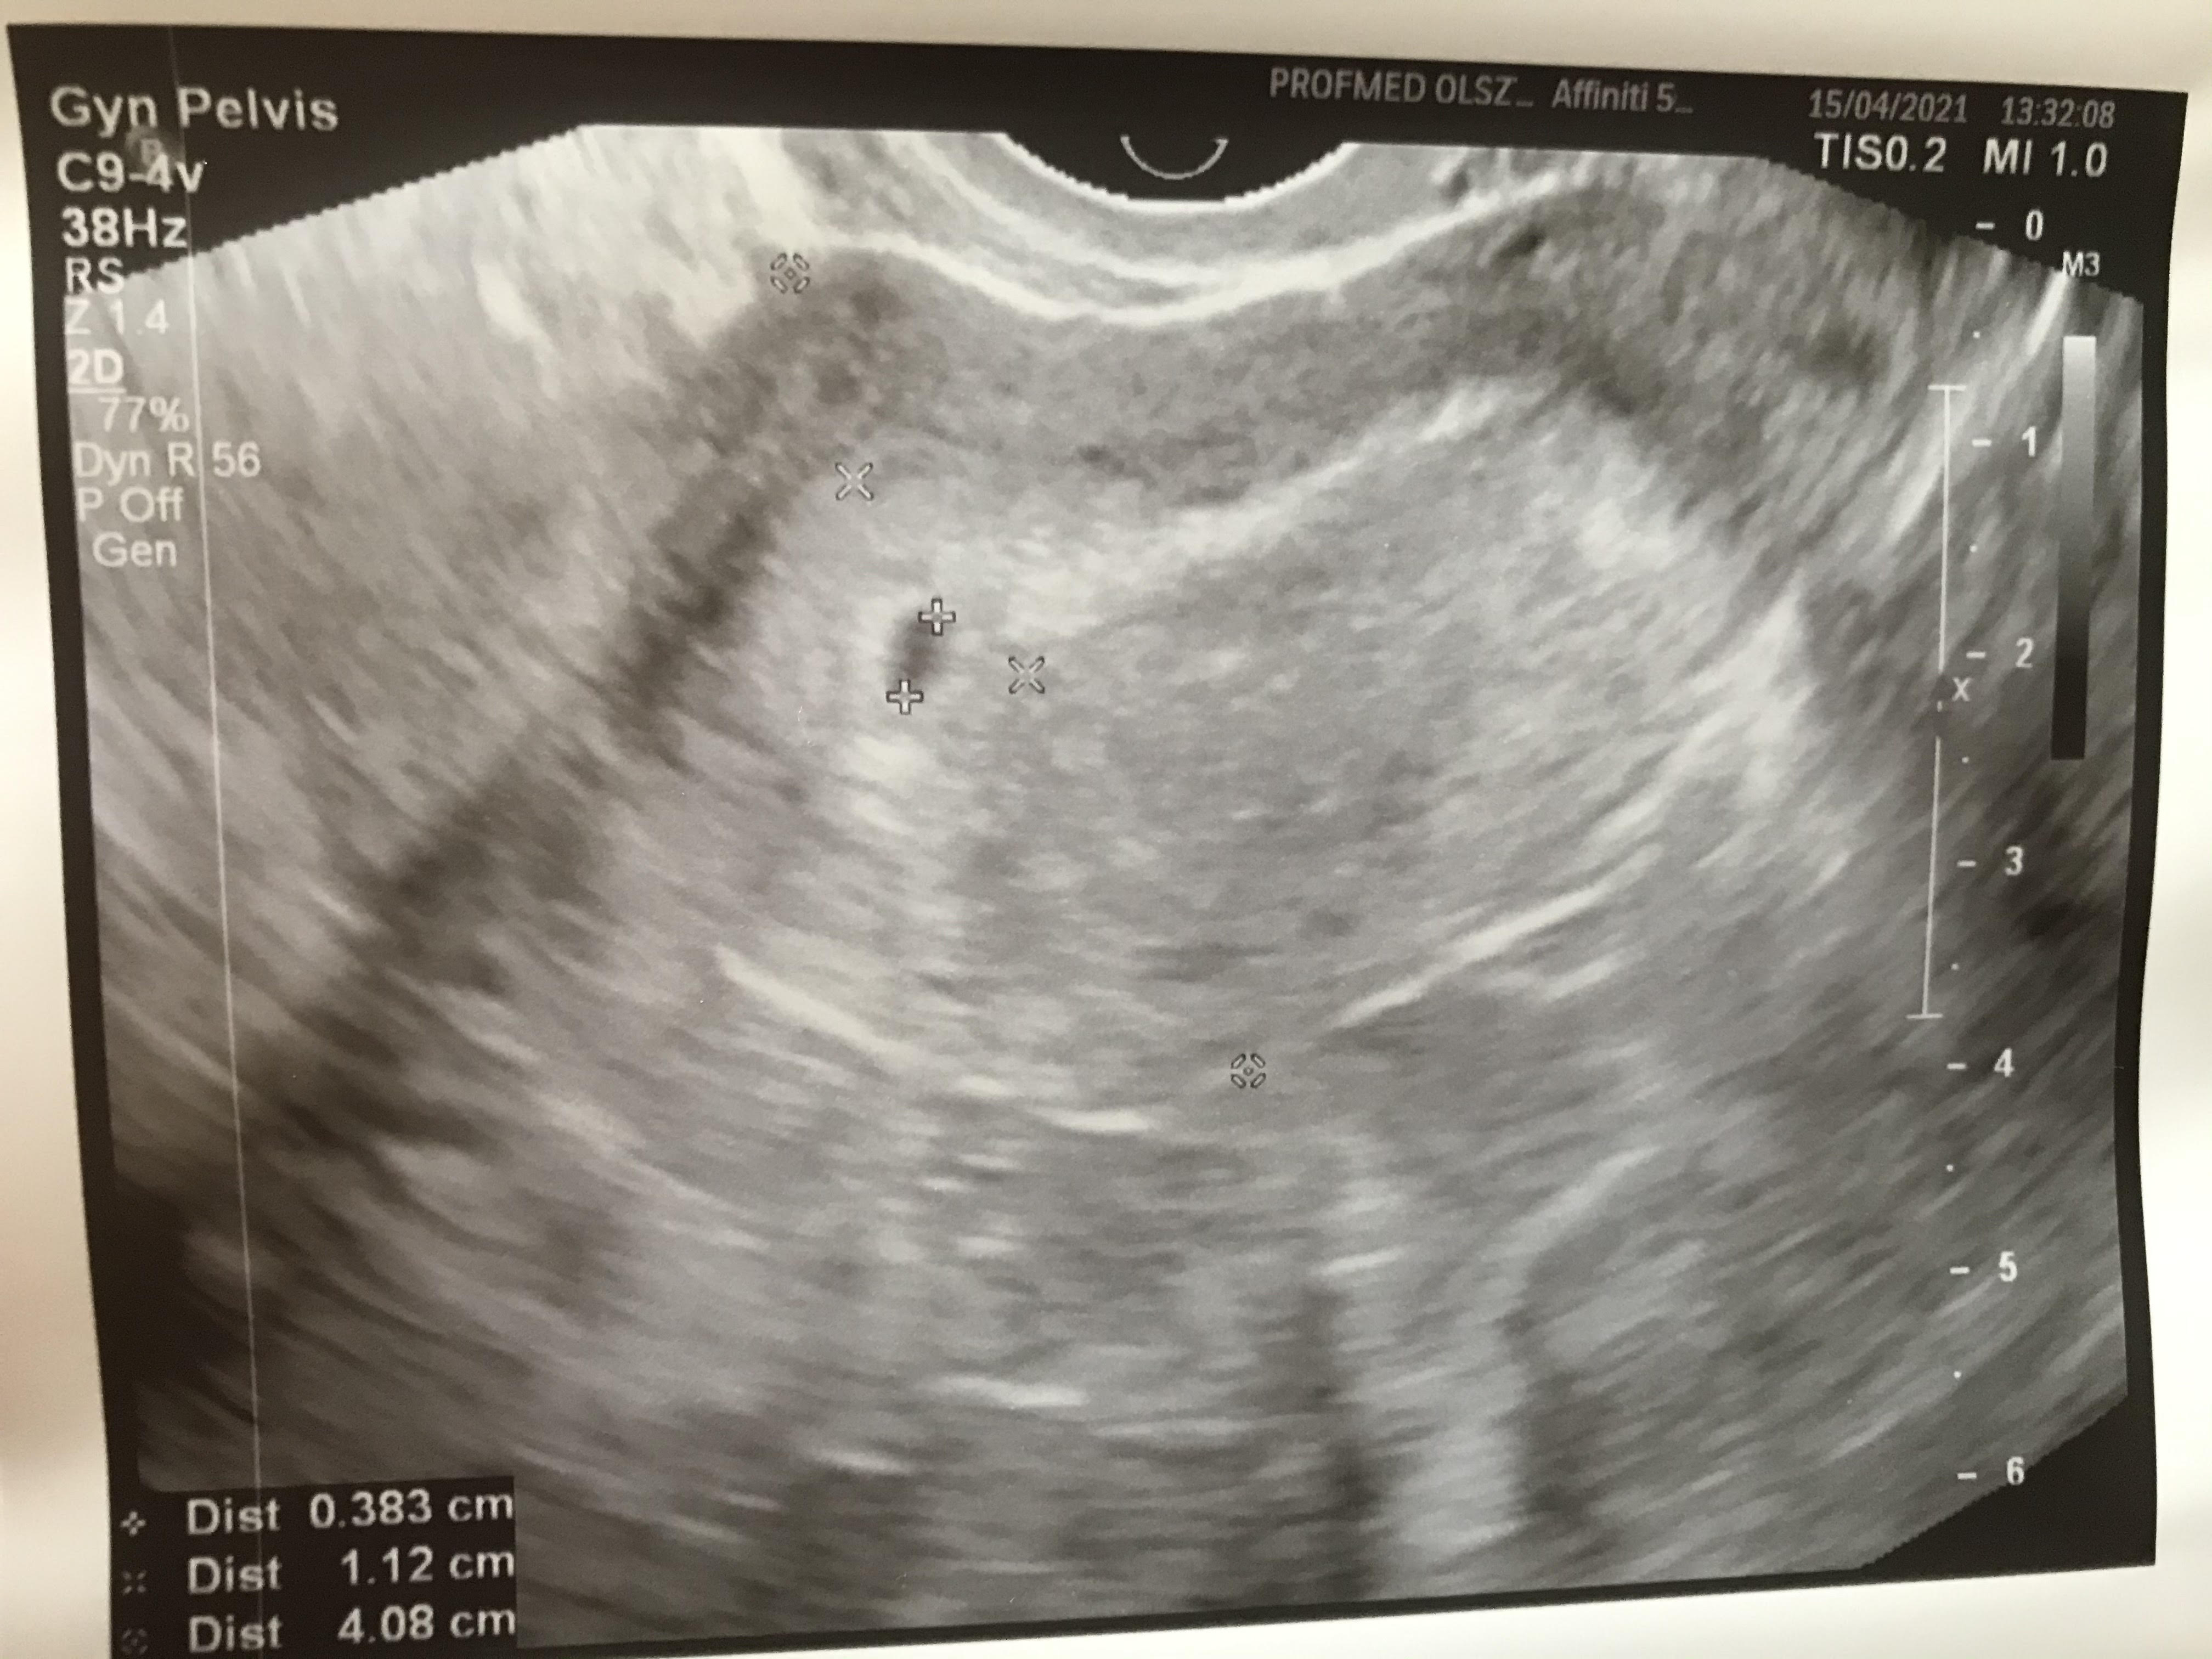

Właśnie wróciłam od lekarza :D

Dziś 4+5 i jest widoczny pęcherzyk 3,8mm.

Wiem, że jest szybko i mam wrócić za 2 tyg, żeby było widać coś więcej ale i tak jestem spokojniejsza, że jest na swoim miejscu ❤️

• usg.jpg